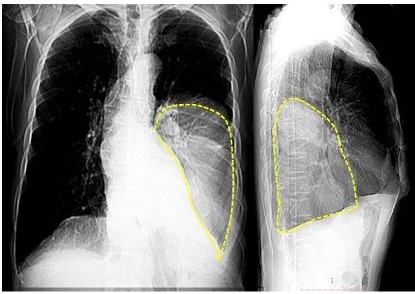

Paciente masculino de 75 años de edad, sin antecedentes de hábitos tabáquicos, ni patológicos de importancia, quien consulta por presentar tos persistente de tres meses de evolución sin secreción que no responde al tratamiento, sin otra sintomatología (dolor y/o dificultad para respirar), motivo por cual consulta a facultativo quien indica estudios de imágenes: radiografía de tórax en proyección anteroposterior y lateral en donde aprecia imagen que ocupa todo el tercio inferior del hemitórax izquierdo (Figura 1 A y 1B).